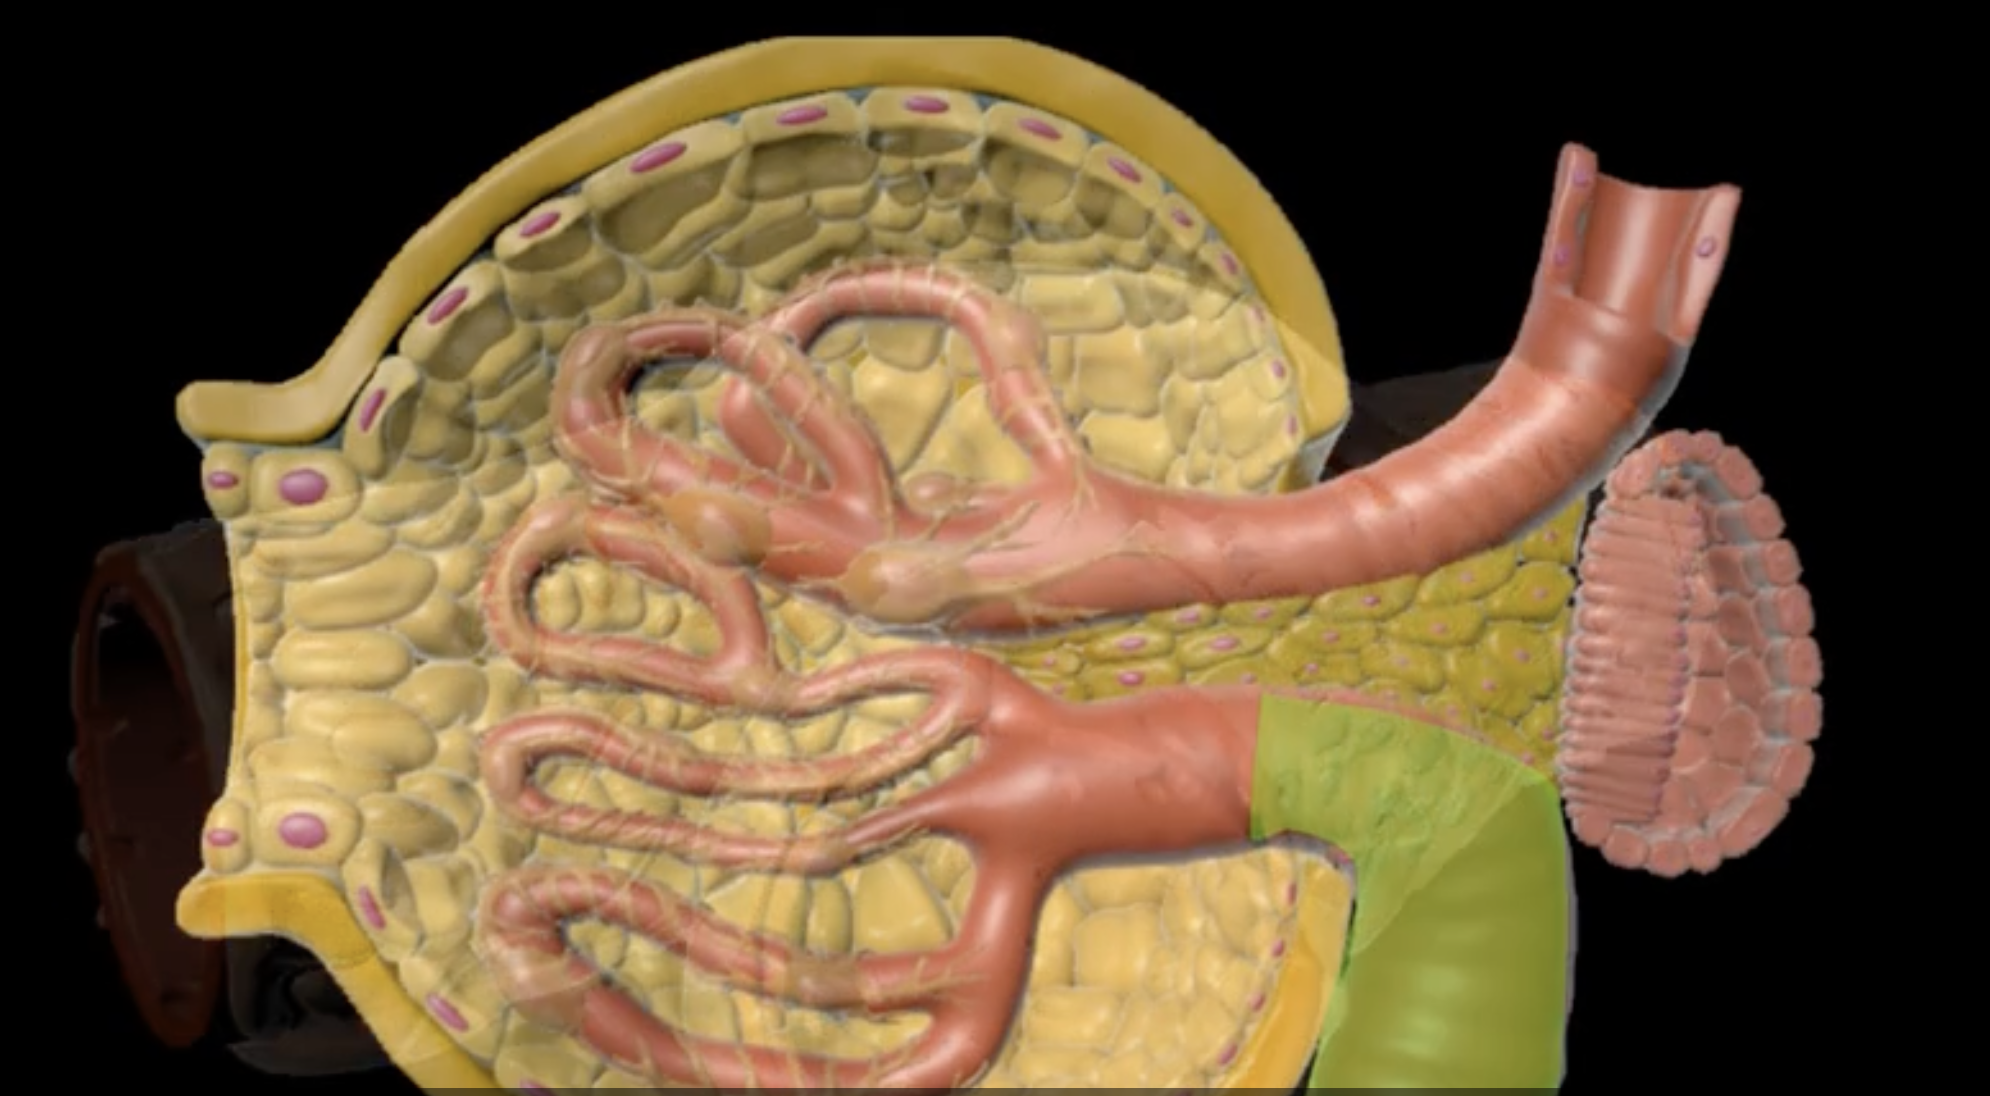

yellow: cortical nephron

blue: juxtamedullary nephron

yellow:

blue:

nephron

functional unit of the kidney

green: renal corpuscle

purple: renal tubule

green:

purple:

blue: glomerulus

orange: Bowman’s capsule

orange: